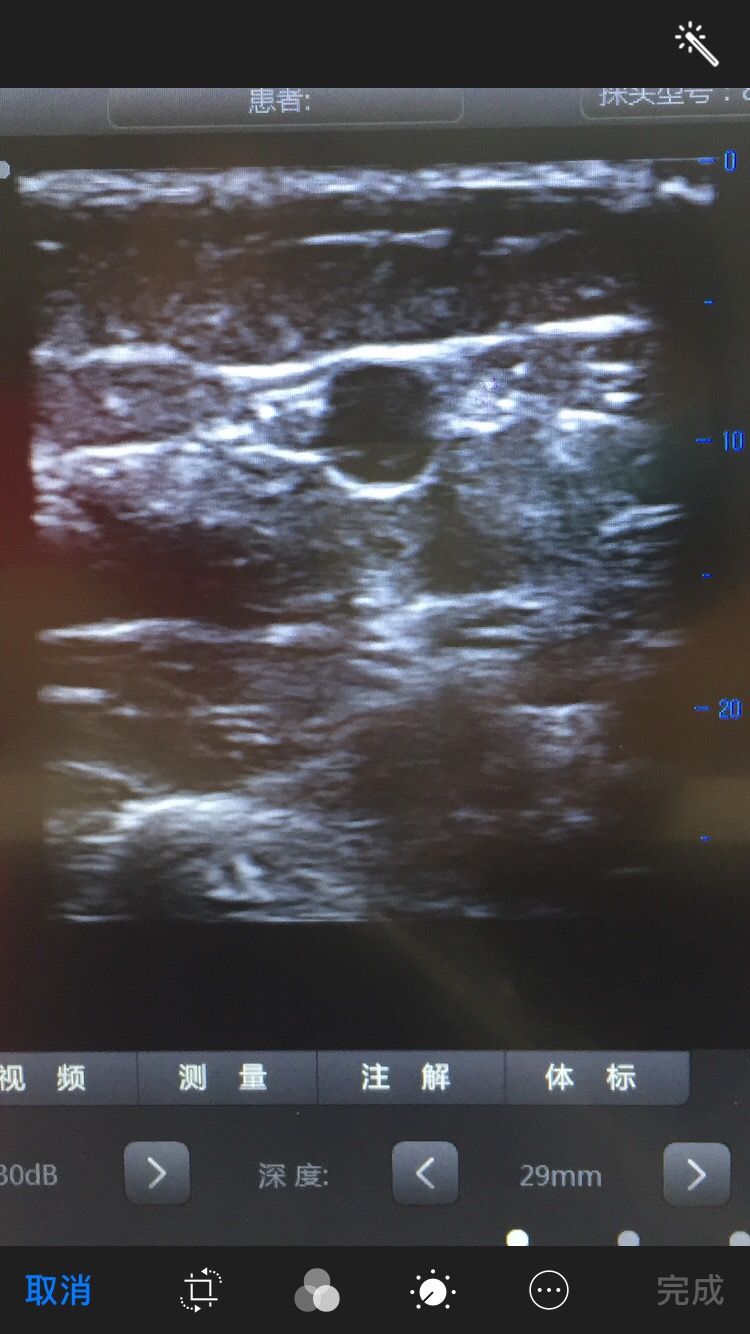

8月17日,漯河市三院为一名88岁患者在无菌超声引导下成功置入pIcc导管。

该患者88岁,外周静脉条件差,右手臂外展受限,市三院内二科在谷旭红主任和李艳梅护士长的帮助下,由专科护士宋永向以左手臂贵要静脉为穿刺点、在无菌超声引导下,成功为患者置入pIcc导管,置管后沿静脉走行到上腔静脉并通过拍片确定导管尖端位于T7。填补了市三院内二科pIcc置管技术的空白,标志着市三院内二科护理技术水平迈上了新的台阶。